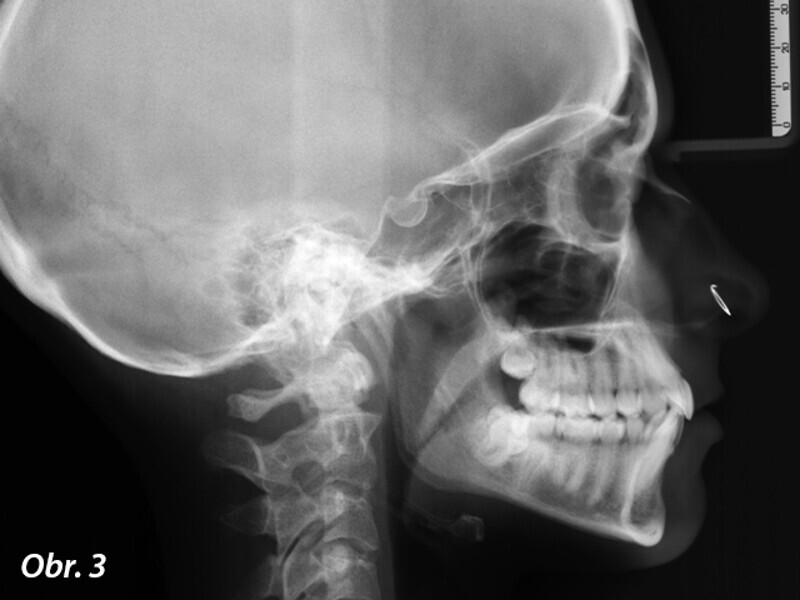

Ortodontická léčba komplexních případů malokluze pomocí průhledných alignerů